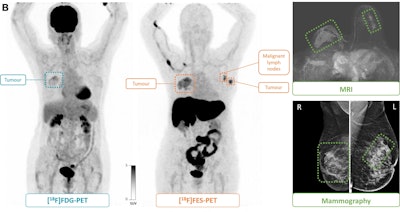

(B) F-18 FDG-PET maximum intensity projection, F-18 FES-PET maximum intensity projection, breast MRI scan, and mammogram in an 81-year-old female participant who presented with a tumor in the right breast. F-18 FES-PET scan shows a second primary tumor (grade 1, lobular) in the left breast and malignant lymph nodes (T2N1M0) that are not visible on the F-18 FDG-PET scan. The tumor in the right breast (T4N0M0, grade 3 ductal carcinoma) is visible on both PET scans. All lesions had also been identified at mammography and MRI. Image and caption courtesy of the RSNA.(B) F-18 FDG-PET maximum intensity projection, F-18 FES-PET maximum intensity projection, breast MRI scan, and mammogram in an 81-year-old female participant who presented with a tumor in the right breast. F-18 FES-PET scan shows a second primary tumor (grade 1, lobular) in the left breast and malignant lymph nodes (T2N1M0) that are not visible on the F-18 FDG-PET scan. The tumor in the right breast (T4N0M0, grade 3 ductal carcinoma) is visible on both PET scans. All lesions had also been identified at mammography and MRI. Image and caption courtesy of the RSNA.